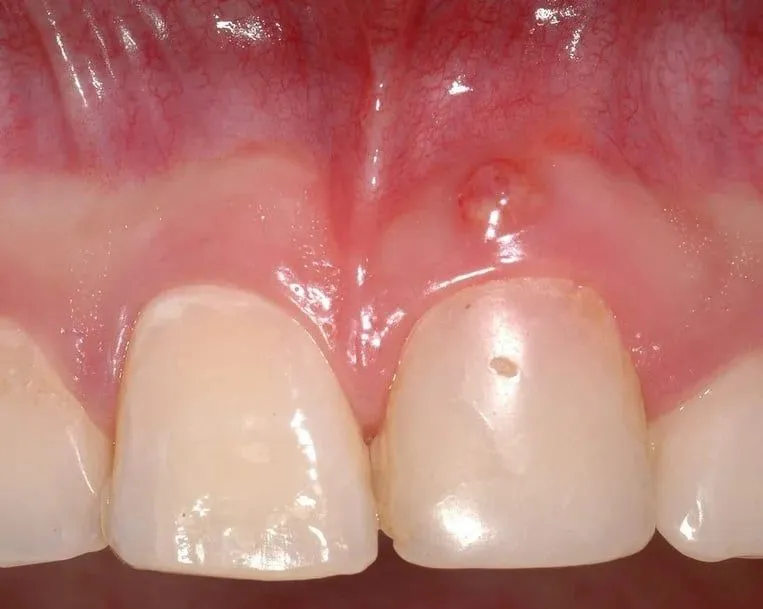

Jak wygląda ropień? Kluczowe cechy wizualne, które pomogą Ci go zidentyfikować

Rozpoznanie ropnia na dziąśle po samym wyglądzie jest kluczowe dla szybkiej reakcji. Zazwyczaj ropień manifestuje się jako bolesna, wyraźnie widoczna wypukłość na dziąśle. Może przybierać różne formy od niewielkiego pęcherzyka, przez guzek, aż po większą krostę. To, co go wyróżnia, to przede wszystkim kolor i konsystencja. Często jest intensywnie zaczerwieniony, a w jego centrum można dostrzec żółtawą lub zielonkawą treść ropną, która prześwituje przez cieńszą błonę śluzową. Zmiana ta jest zazwyczaj wyraźnie odgraniczona od zdrowej tkanki dziąsła, co ułatwia jej identyfikację. Pamiętaj, że dotknięcie ropnia jest zazwyczaj bardzo bolesne, a sama okolica jest opuchnięta i twarda w dotyku.

- Kolor: Intensywnie zaczerwieniony, z żółtawą lub zielonkawą treścią ropną widoczną w centrum.

- Kształt: Wypukłość, pęcherzyk, guzek lub krosta.

- Konsystencja: Opuchnięty, twardy, bardzo bolesny przy dotyku.

- Odgraniczenie: Zazwyczaj wyraźnie odgraniczony od zdrowej tkanki dziąsła.

Przetoka ropna: gdy organizm sam tworzy ujście dla infekcji

Jedną z częstych konsekwencji długo utrzymującego się ropnia jest powstanie przetoki ropnej. Jest to swego rodzaju "kanał", który organizm tworzy, aby umożliwić odpływ ropy z głębszych tkanek na zewnątrz, najczęściej do jamy ustnej. Przetoka wygląda jak mała krostka lub otwór na dziąśle, z którego okresowo lub stale wydobywa się ropa. Choć jej pojawienie się może przynieść ulgę w bólu (ponieważ ciśnienie w ropniu spada), nie oznacza to w żadnym wypadku wyleczenia! Przetoka jest jedynie objawem przewlekłej infekcji, która nadal toczy się w tkankach. Wymaga ona leczenia stomatologicznego, aby usunąć źródło zakażenia i zamknąć przetokę.